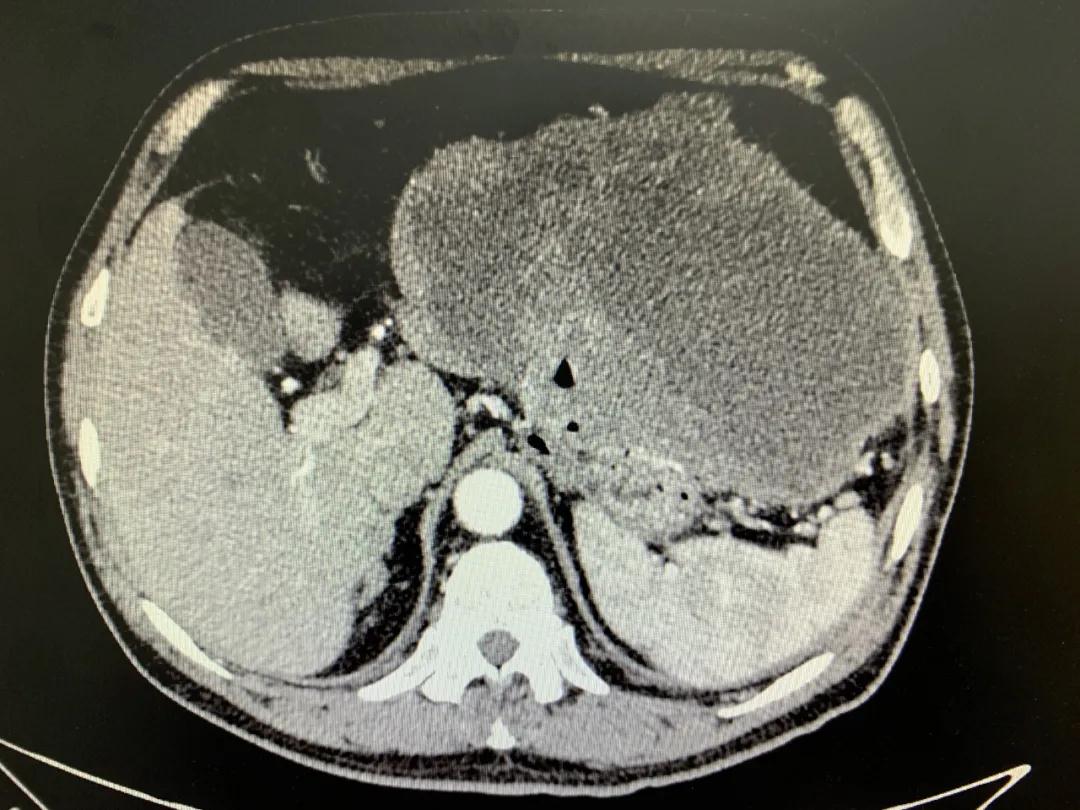

患者入院時(shí)血紅蛋白數(shù)值仍持續(xù)下降,出現(xiàn)失血性休克表現(xiàn),危及生命。消化外科二病區(qū)蔡磊主任接診后,組織科室迅速對(duì)患者進(jìn)行了全面的檢查。CT提示腫瘤大小約19.3*10.3cm,腫瘤內(nèi)提示大量積血。結(jié)合相關(guān)檢查,考慮為罕見的巨大胃間質(zhì)瘤合并出血。

蔡磊主任團(tuán)隊(duì)立即為患者安排了手術(shù),術(shù)中發(fā)現(xiàn)腫瘤巨大,占據(jù)大部分胃壁,胃腔內(nèi)殘存血液達(dá)3400ml之多,且多為新鮮活動(dòng)性出血,給手術(shù)增加了非常大的難度。但蔡磊主任團(tuán)隊(duì)克服困難,在麻醉手術(shù)中心的幫助下,終于將腫瘤完整切除,術(shù)后稱量腫瘤達(dá)10斤重!